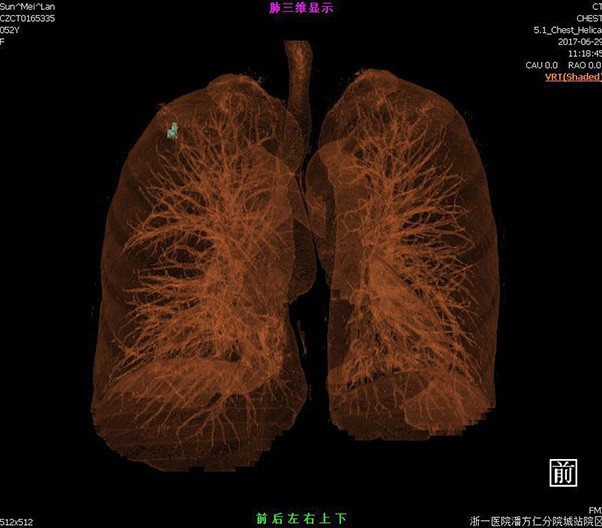

Lung reverse scanning eliminate respiratory motion artifact

NDI NanoDose Iteration Algorithm (NDI) is an innovative iterative technique for image reconstruction that takes full advantage of deep learning in anatomical structure in image space as well as model-driven iteration involving tube and detector in projection space, with the aim to generate sharp and high-resolution images at the lowest possible dose.